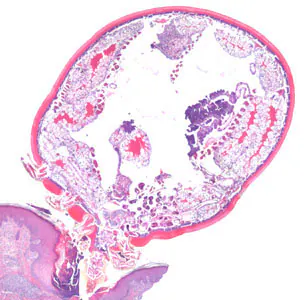

An 81-year-old man, with a previous history of basal-cell carcinoma on his upper right arm and shoulder, presented with a small protuberance in the hollow of his left knee. A biopsy specimen was collected, sectioned, and stained with hematoxylin-and-eosin (H&E). Figures A–D show what was observed by the attending pathologist. What is your diagnosis? Based on what criteria?

Figure A